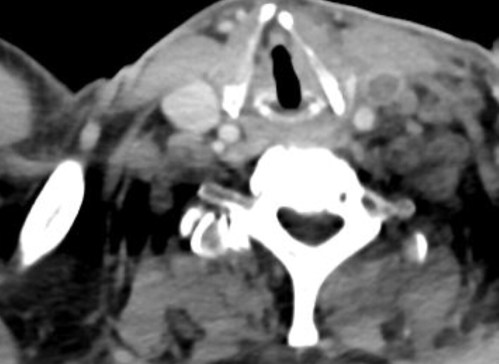

A previously healthy young man (early 20’s) presented with severe left-sided sore throat, followed a day later by fever with chills, for 4 days. This was accompanied by lethargy and complete loss of appetite. He had seen a family doctor on the first day and was prescribed painkillers and antipyretics without significant relief. On clinical […]